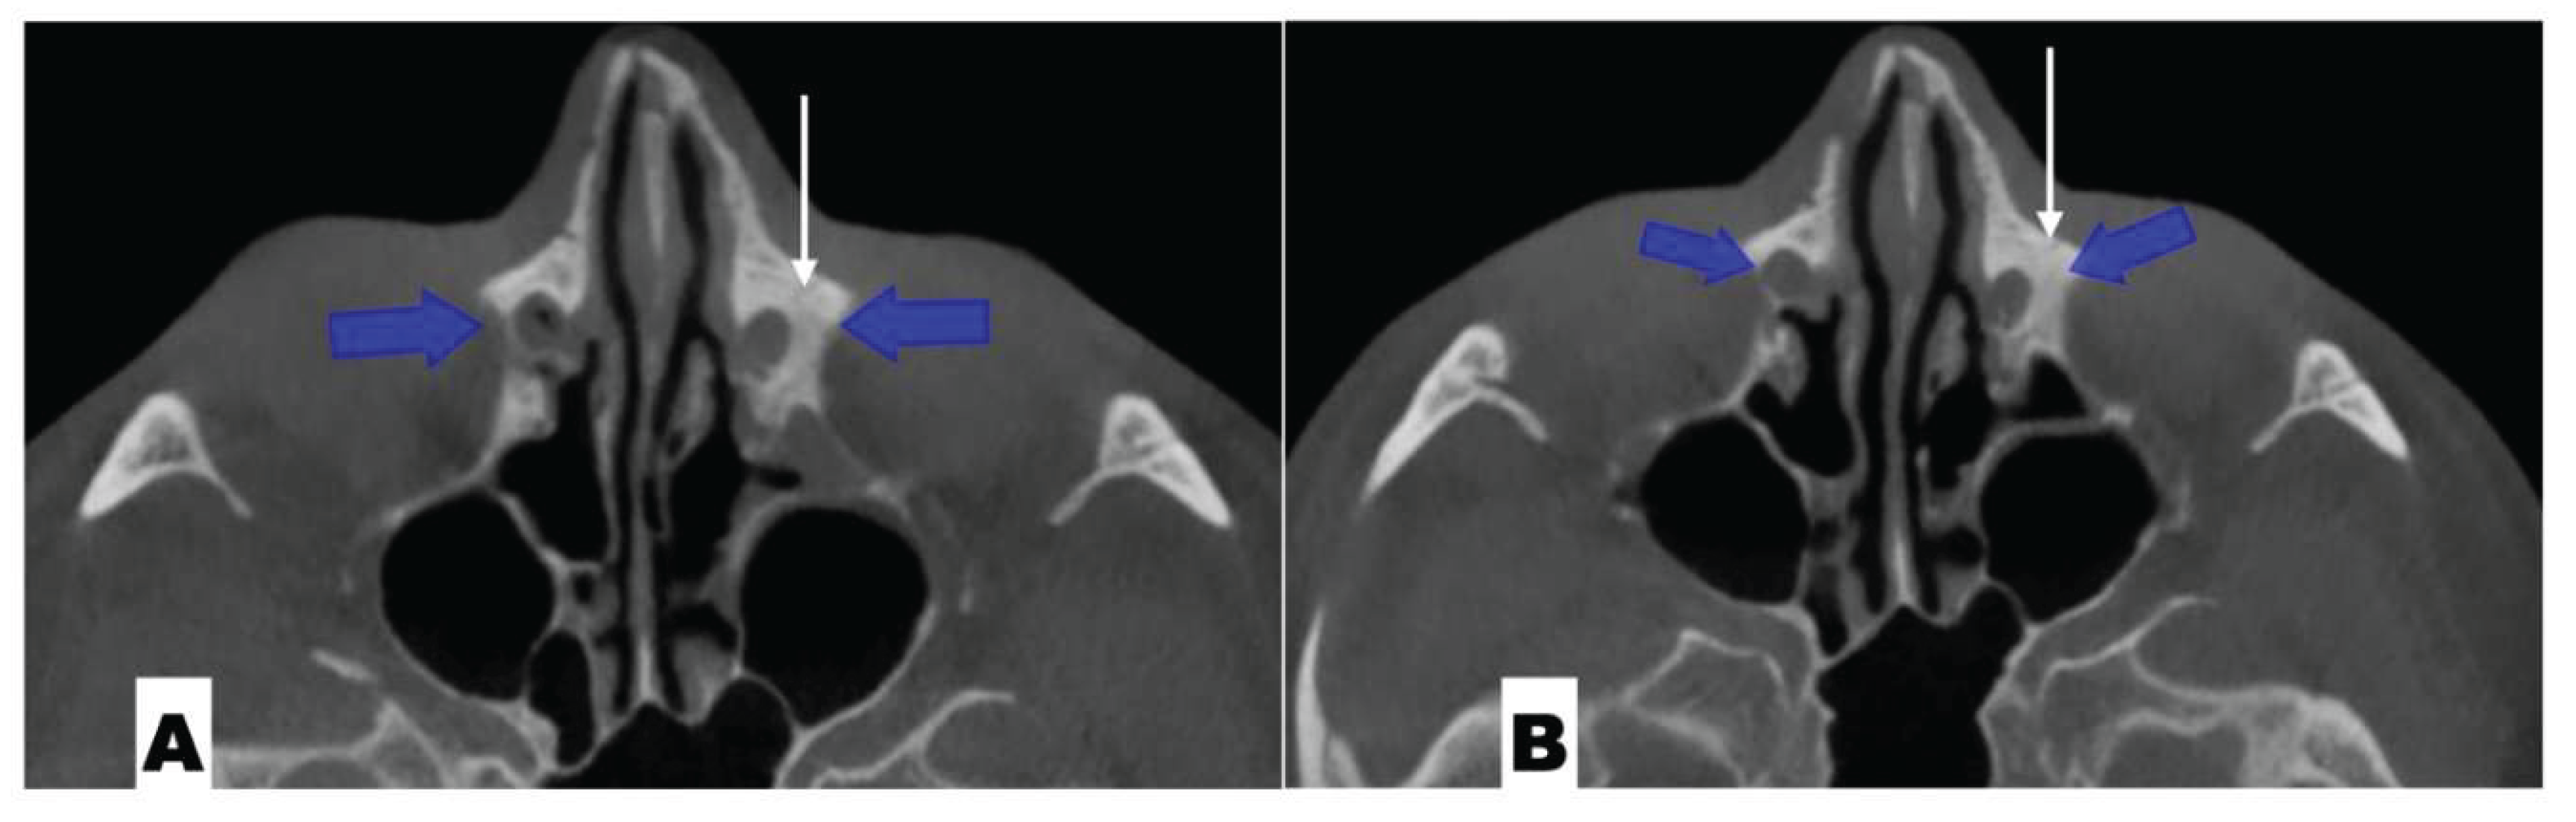

Background: While mini-screw-assisted rapid palatal expansion (MARPE) is effective for correcting maxillary transverse deficiency in adults, perimaxillary suture disarticulation—particularly at the pterygomaxillary junction—can be inconsistent. This study evaluates skeletal and dentoalveolar outcomes of a novel 3D-guided midpalatal piezocorticotomy-assisted MARPE protocol, focusing on expansion symmetry and pre-existing asymmetries. Methods: Three adult patients were retrospectively analyzed after treatment with 3D-guided midpalatal piezocorticotomy-assisted MARPE expansion and one with non-guided midpapalatal piezocorticotomy and MARPE expansion. Surgical guides were digitally designed using CBCT data to align with the nasal septum orientation in multiple planes. Perimaxillary suture disarticulation was measured pre- and post-expansion, and dentoalveolar changes were evaluated. Post-expansion asymmetries were addressed using directly printed aligners. Results: Complete midpalatal suture separation (mean 8.48 mm), involving both anterior and posterior nasal spine regions, was achieved in one patient. Bilateral pterygomaxillary disarticulation averaged 1.06–1.23 mm, resulting in forward–outward rotation of the nasomaxillary complex. Additional separation occurred at the frontonasal (2.03 mm) and vomeromaxillary (1–2 mm) sutures, with no significant changes in orbital or peri-orbital sutures. One patient presented with pre-existing dentoalveolar asymmetry, which intensified the perceived post-expansion imbalance but was successfully corrected with directly printed aligners. In the second case, 5.6 mm of suture separation resulted in a limited lateral nasal width increase (<1.5 mm), while maxillary base expansion exceeded 6 mm. A significant canine plane cant (1.2 mm) and divergent axial inclinations of the maxillary central incisors relative to the palatal plane were also observed. In the second case, a non-impactful palatal bone fracture with asymmetric displacement of the left palatine fragment was documented. After 16 months of aligner therapy, all cases exhibited favorable remodeling of the palatal structures, midpalatal suture, and alveolar processes, accompanied by improved dental alignment, occlusal plane symmetry, and mandibular dentoalveolar adaptation. The dento-alveolar expansion achieved in the third case over the course of 16 months of treatment was approximated at 4 mm. The fourth case showed consistent improvement with direct printed aligners after MARPE midpalatal diasrticulation of 11 mm after experiencing minor bone fracture. Conclusions: Human skulls exhibit considerable variability between the left and right sides, which can influence spatial balance. Pre-existing cranial asymmetries appear to be the primary contributors to asymmetry following MARPE treatment. Careful evaluation of dentoalveolar discrepancies and axial tooth inclinations is essential for preventing and managing potential asymmetric dental arch outcomes during the post-expansion phase. Although peri-maxillary bone fractures are relatively uncommon, their occurrence is influenced by multiple factors. Adjunctive techniques, such as 3D-guided midpalatal piezocorticotomy, show promise in significantly lowering the risk of intra-expansion peri-maxillary fractures.

| Suture nomenclature | Amount of disarticulation |

|---|---|

| Midpalatal | 8.48 mm |

| Palatinomaxillary (transverse) | none |

| Nasomaxillary | 1-2 mm |

| Zygomaticomaxillary | none |

| Lacrimomaxillary | none |

| Ethmoidomaxillary | none |

| Sphenomaxillary | none |

| Vomeromaxillary | 1-2 mm |

| Frontomaxillary | 2.5 mm |

| Pterygomaxillary | 1.06-1.23 mm |

| Frontonasal | 2.03 mm |

| Frontozygomatic | None |